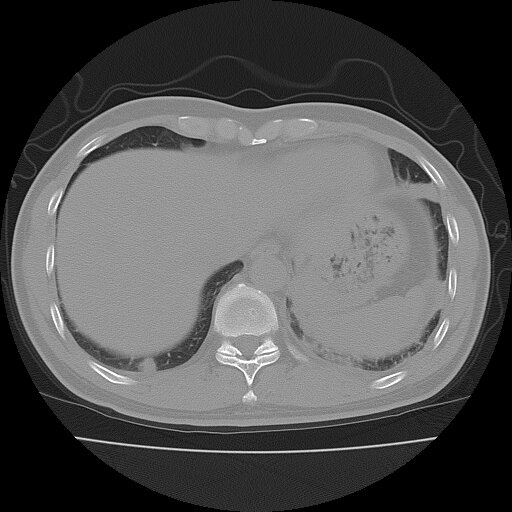

左侧胸痛,无其他病史

炎性假瘤

考虑肺内炎性肉芽肿,少量胸水。

转移瘤

考虑两肺感染性病变;建议抗炎治疗后复查。

暂考虑两肺感染性病变,左侧少量胸水;建议抗炎治疗后复查

首先考虑双肺感染性病变,左侧少量胸水,见过类似病例,抗炎后都吸收了

右侧胸膜下多发小结节——支持考虑:炎性假瘤!

警惕转移灶